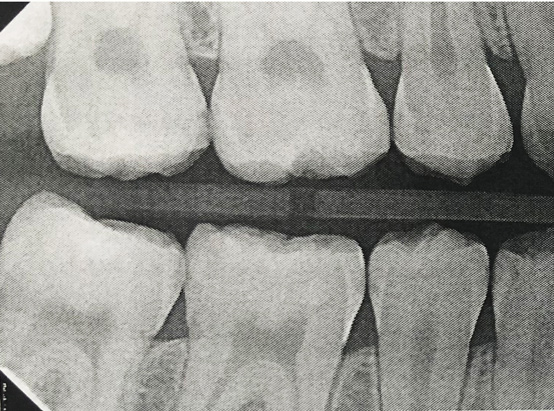

Fig 3. Three thin soft dental picks were used simultaneously for SDF proximal surface saturations in a teenaged patient (Fig 3). After 60 seconds, the treated regions were covered with 5% fluoride varnish (Fig 4). A comparison can be seen of pre-SDF-treatment bitewing films (Fig 5) and 8-month post-SDF bitewing films (Fig 6) for the patient shown in Fig 3 and Fig 4. Radiolucencies were similar or improved, except for contact of maxillary first and second molars.

Fig 5. Three thin soft dental picks were used simultaneously for SDF proximal surface saturations in a teenaged patient (Fig 3). After 60 seconds, the treated regions were covered with 5% fluoride varnish (Fig 4). A comparison can be seen of pre-SDF-treatment bitewing films (Fig 5) and 8-month post-SDF bitewing films (Fig 6) for the patient shown in Fig 3 and Fig 4. Radiolucencies were similar or improved, except for contact of maxillary first and second molars.

Figure 5